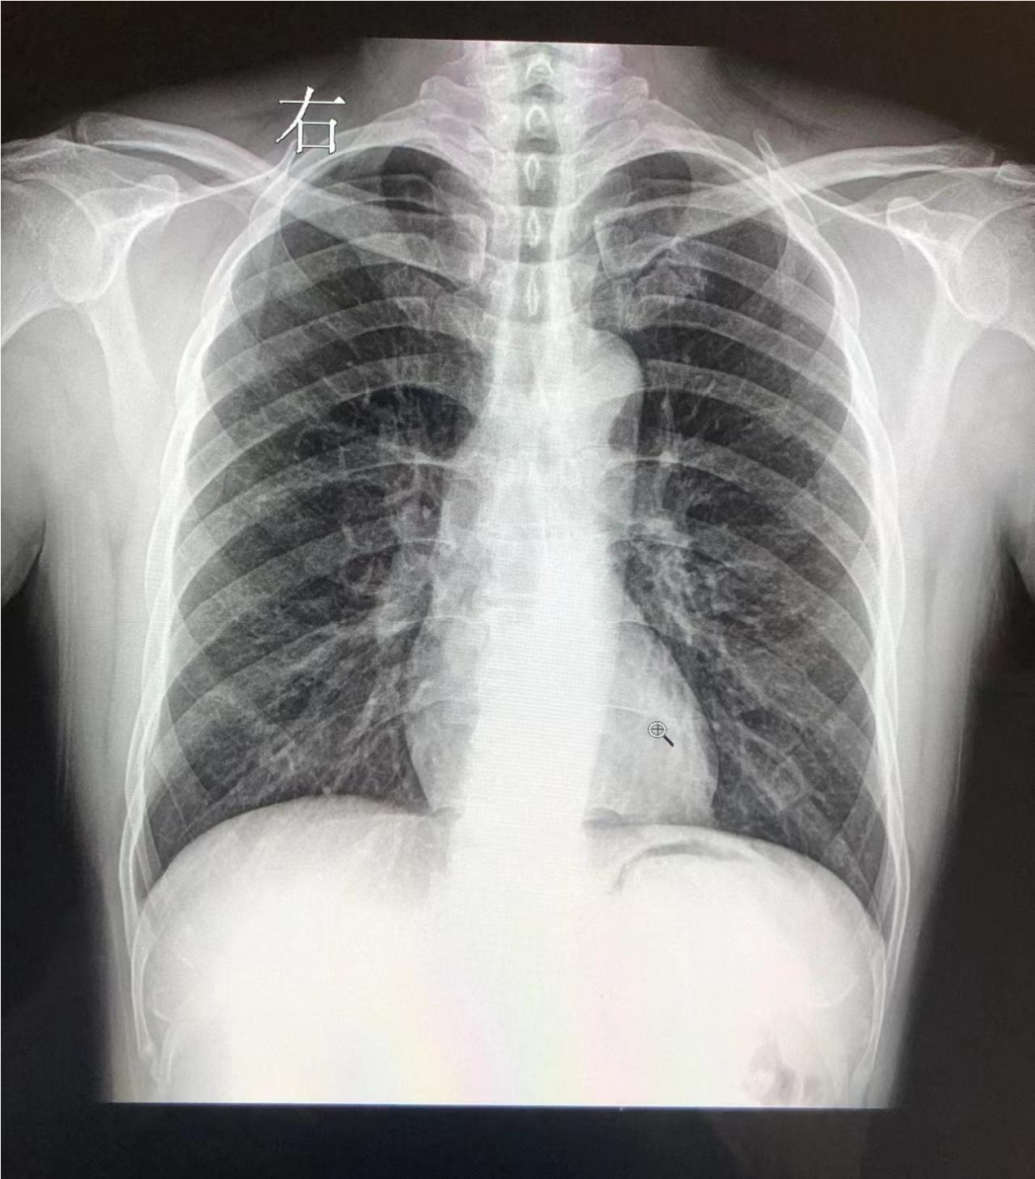

(胸片异常影像)

当X线透过人体后投射到采集板上所形成的黑白影像,是二维叠加的图像,所以肺部早期病变是有可能被肋骨、心影、胸壁软组织等重叠所干扰,肺部小结节也容易被隐藏,胸片一般只能查到15~20mm的肿瘤。在实际工作中,当胸片发现了肺部异常,需要做CT进一步排查,进一步确诊还要做 增强CT 。